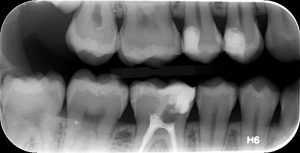

2. FULL-MOUTH ΟΠΙΣΘΟΦΑΤΝΙΑΚΕΣ  ΑΚΤΙΝΟΓΡΑΦΙΕΣ

Πρόκειται για ένα σετ 14-16 οπισθοφατνιακών ακτινογραφιών, οι οποίες λαμβάνονται διαδοχικά προκειμένου να απεικονιστούν όλα τα δόντια της άνω και κάτω γνάθου.